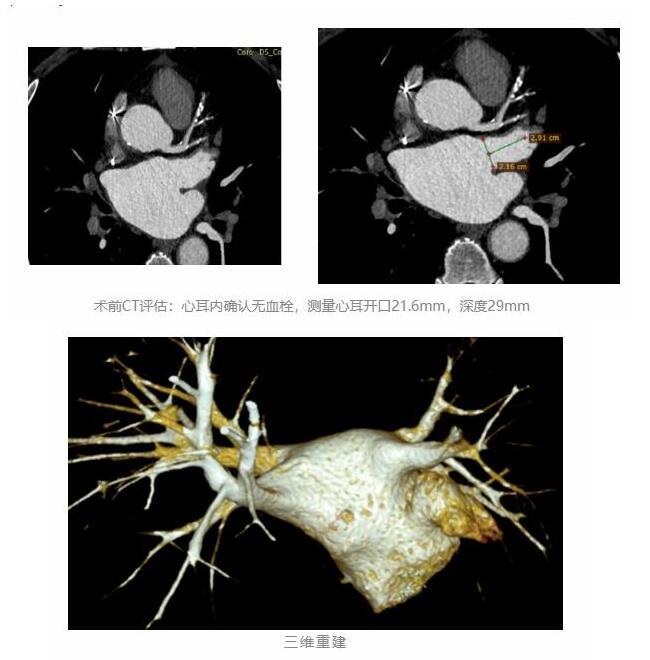

心内科一病房主任宋湘教授团队在术前积极完善各项辅助检查,与患者及家属充分沟通,考虑到患者年龄、目前病情,结合周围血管、脑血管情况等,最终决定采用“房颤射频消融+左心耳封堵”,“一站式”解决患者的房颤及脑卒中问题。

心耳开口22mm,深度28.4mm,考虑到患者心耳上下缘极不对称形状,选择了合适型号封堵器。团队密切配合,精准操作,完美封堵。术后患者恢复为窦性心律,心慌、气短症状明显缓解,两天后顺利出院。